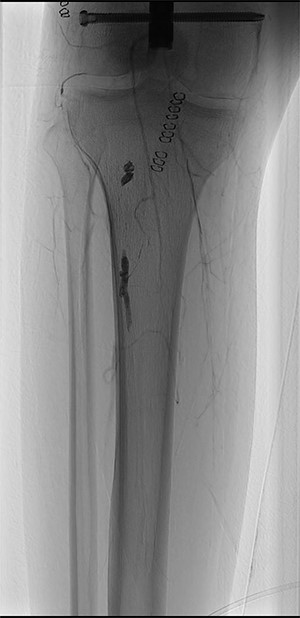

At the Doppler examinations after 2 and 12 months, triphasic-flow of the entire vascular artery axe of the lower right limb was detected (Fig. 4).

Duplex ultrasound made after 2 months, showing triphasic flow of the right popliteal artery.